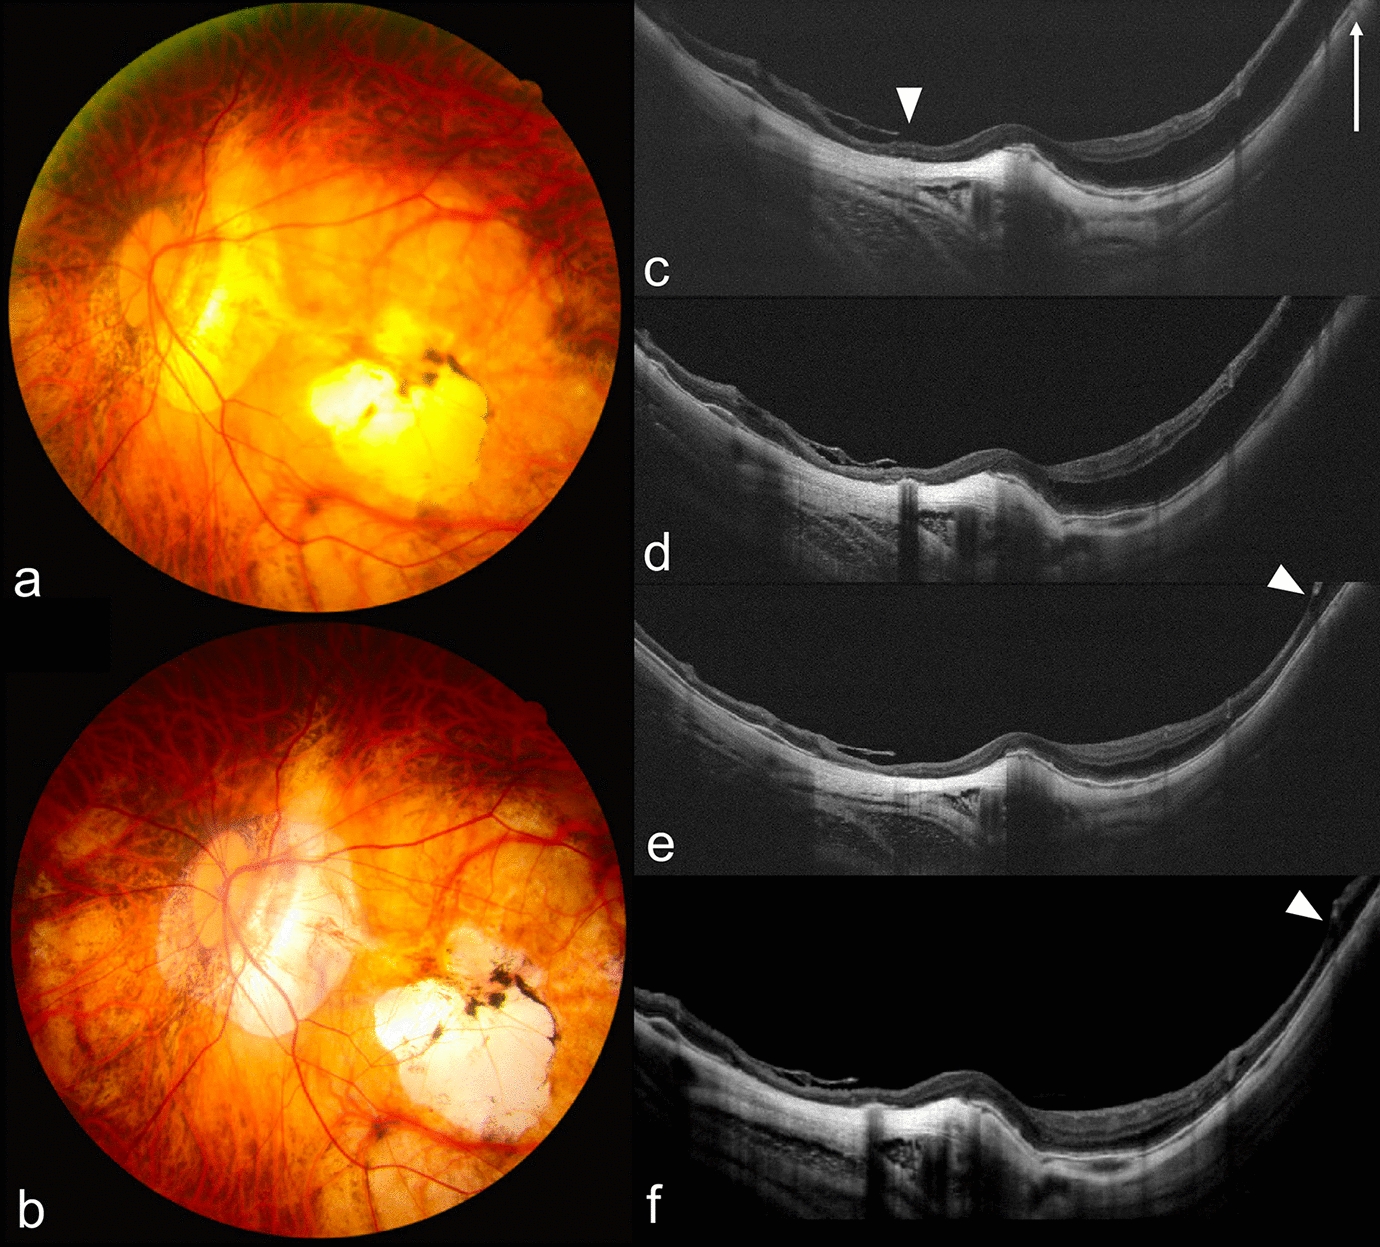

Of the 295 eyes, 13 showed progression, with 15.4% of these progressing to FTMH (1 case is shown in Fig. 1), 15.4% to FD (1 case is shown in Fig. 2), 30.8% to macular hole retinal detachment (MHRD), 7.7% to LMH, and 30.8% to other conditions at risk of vision threatening, such as foveoschisis shaped like a champagne flute [12, 13, 26] (1 case is shown in Fig. 3). Consequently, these eyes received surgical intervention at 12.7 ± 9.1 months (range 2–34 months, median 10 months) after initial injection. (Table 2). One eye (Fig. 3) received IV perfluoropropane (C3F8) [27, 28] and the other 12 eyes received pars plana vitrectomy combined with the inverted ILM flap technique [29, 30] (5 eyes; 1 case is shown in Fig. 1), the center non-peeling ILM surgery technique [3134] (3 eyes), or simple ILM peeling (4 eyes; 1 case is shown in Fig. 2). Of the 13 eyes with progression, 11 (84.6%) had MRS at baseline. Risk factors for vision-threatening MRS requiring surgical intervention in eyes with progression and onset of MRS were evaluated by using logistic regression models (Table 3). AL, AL of fellow eye, initial CFT, myopic maculopathy category at baseline, and presence of foveoschisis, inner retinal schisis, ERM, and LMH at baseline were identified to be risk factors, while intravitreal ranibizumab (IVR) and presence of retinal hemorrhage at baseline were protective factors. Eyes requiring surgical intervention compared to those with no need of surgical intervention had poorer BCVA at 1 month after injection (logMAR 0.757 ± 0.363 vs. logMAR 0.510 ± 0.410, p = 0.026), at 6 months (logMAR 0.799 ± 0.402 vs. logMAR 0.521 ± 0.451, p = 0.011), at 1 year (logMAR 0.882 ± 0.528 vs. logMAR 0.530 ± 0.413, p = 0.012), and at the last follow-up visit (logMAR 1.038 ± 0.767 vs. logMAR 0.667 ± 0.624, p = 0.030), and had greater CFT at 1 month (370.7 ± 147.5 vs. 274.9 ± 57.9 µm, p = 0.009), at 3 months (353.4 ± 129.9 vs. 268.8 ± 56.6 µm, p = 0.003), and at 6 months (415.8 ± 196.5 vs. 274.5 ± 52.1 µm, p = 0.001). In addition, the former had higher ratios of categories 3 and 4 myopic maculopathy at the last follow-up visit. We also found that there was no association of age, gender, initial BCVA, location of CNV, the number of total injections, the number of intravitreal bevacizumab (IVB), IVR, and intravitreal aflibercept (IVA) injections, as well as presence of lacquer cracks, punctate inner choroidopathy (PIC), staphyloma, MRS, outer retinal schisis, VMT, VMA, and dome-shaped macula at baseline (p > 0.05 for all) (Table 3). In eyes with MRS progression requiring surgery, the progression was found in the following ratios: 53.8% in the outer retinal layers, 23.1% presence of LMH, 7.7% in both the outer and inner retinal layers, 7.7% in inner retinal layers, and 7.7% presence of FTMH.

Fig. 1

Progression of myopic macular retinoschisis (MRS) in the right eye of a 56-year-old woman with myopic choroidal neovascularization (mCNV). a, b Before anti-vascular endothelial growth factor (anti-VEGF) treatment, hyperfluoresence, and leakage of mCNV on late phase of the fluorescein angiography (a) and category 2 myopic maculopathy on color photo (b) are shown. c 7 years after operation, macular atrophy (category 4 myopic maculopathy) was noted on color photo. d, e Before treatment, myopic macular retinoschisis (MRS) with lamellar macular hole (LMH) and juxtafoveal mCNV (arrow) are shown on optical computed tomography (OCT). f 2 years after intravitreal bevacizumab (IVB) treatment, the size of mCNV became smaller (arrow), and best-corrected visual acuity (BCVA) was 20/40. g 32 months after IVB treatment, full-thickness macular hole (FTMH) and new mCNV (arrow) were noted on OCT, and BCVA was 20/200. h 2 years after pars plana vitrectomy and the inverted internal limiting membrane (ILM) flap technique, the FTMH sealed. i 7 years after surgical intervention, the FTMH remained sealed but there were progressive chorioretinal atrophy. BCVA was 20/400